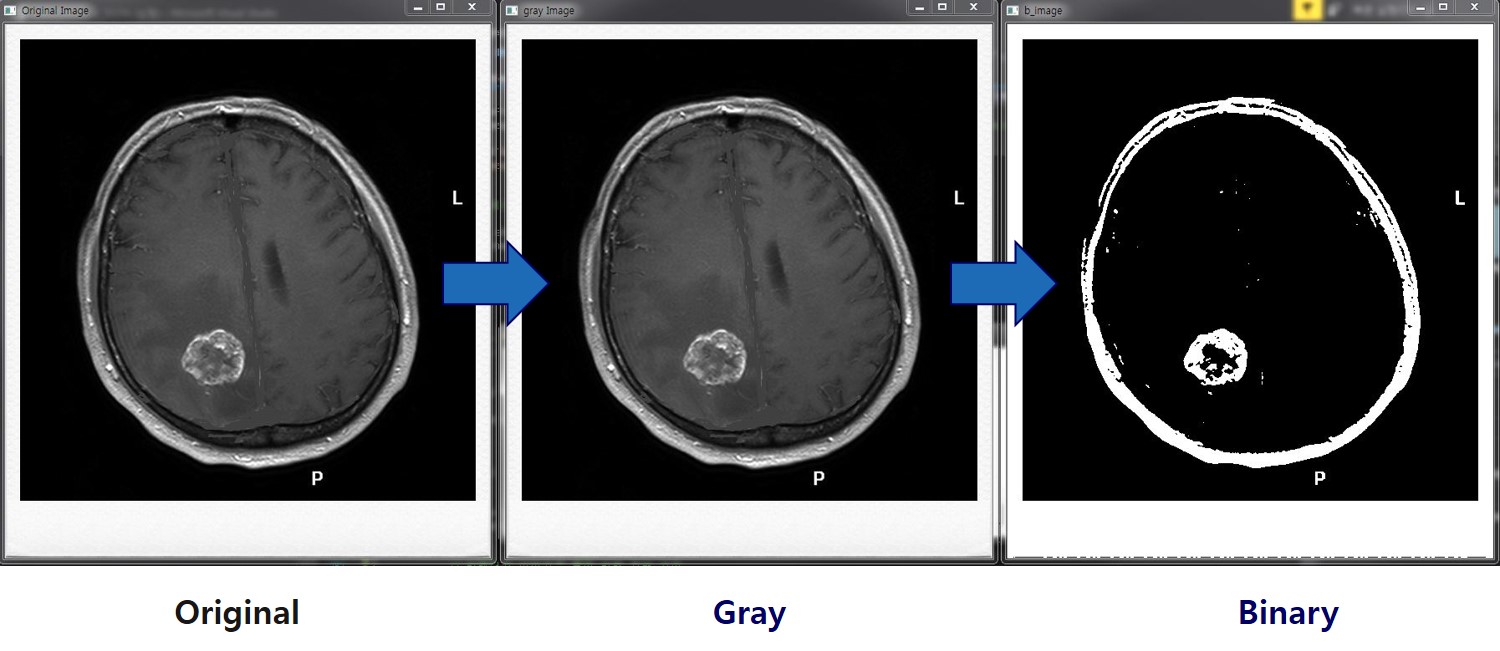

이미지처리를 이용해 DICOM 영상에서 뇌종양 부위 식별에 도움을 주는 알고리즘을 개발함. DICOM 영상데이터를 OpenCV에서 처리가능한 데이터로 변환하고, 이진화 및 모폴로지를 통해 전처리함. 실제 뇌종양 영역의 데이터 분포와 비슷한 양상의 영역을 후보군으로 검출하여 뇌종양 영역 식별을 용이하게함.